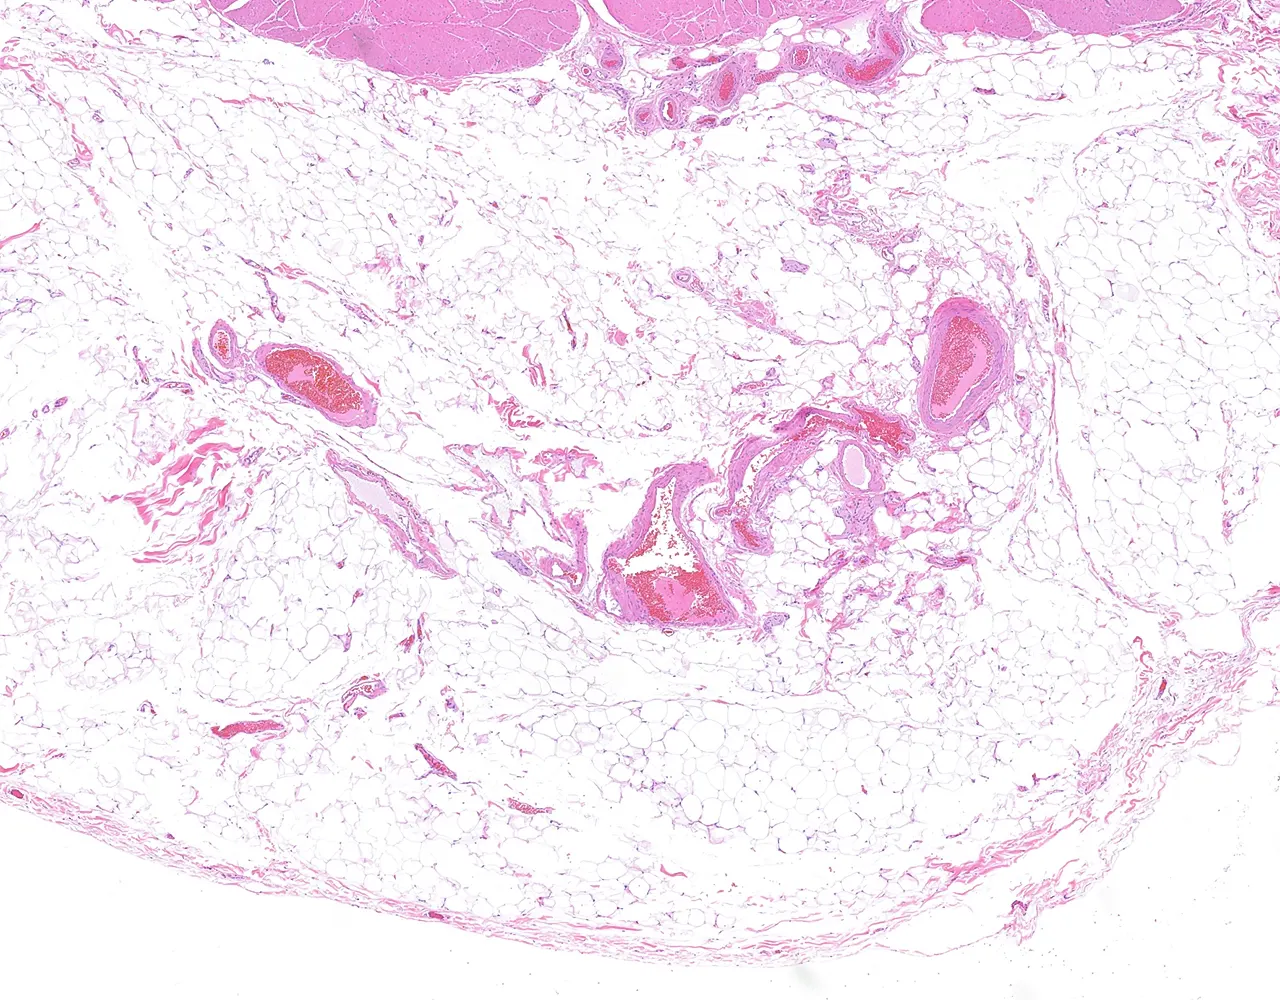

- L’appendice est un diverticule borgne naissant du caecum.

- Il contribue principalement à la fonction immunitaire locale grâce à son abondant tissu lymphoïde et peut également agir comme réservoir du microbiote intestinal normal.